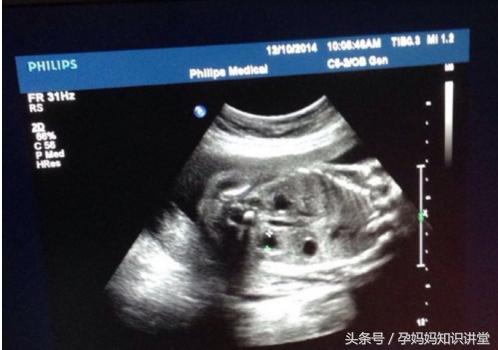

首先,是我们看B超图中是否有三条线,很显然的,如果有三条线存在,那么说明胎儿是女姓,没有则是男娃。

其次,看B超图是否有明显凸出的地方,如果有,而且类似一团菌状,那也很显然,这个胎儿是男性,没有则是女娃。